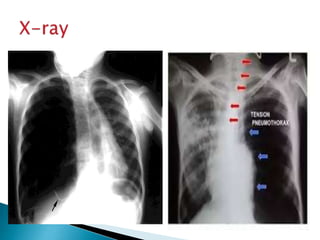

Tension pneumothorax

is a clinical diagnosis

reflecting air under

pressure in the

affected pleural

space.

Do not delay treatment

to obtain radiologic

confirmation.

Tension pneumothorax is aclinical diagnosis reflecting air under pressure in the affected pleural space. Do not delay treatment to obtain radiologic confirmation.